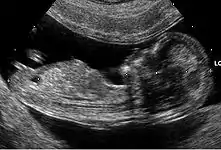

Aucun signe échographique n'est symptomatique de la trisomie 21. Néanmoins, un certain nombre d'anomalies mineures ou majeures qui se rencontrent plus fréquemment dans cette maladie chromosomique peuvent être mis en évidence.

- Anomalies majeures

- des malformations cardiaques (canal atrio-ventriculaire et en particulier) (dans 40 % des cas) ;

- des sténoses digestives (dans 10 à 18 % des cas) (image en « double bulle » de sténose duodénale).